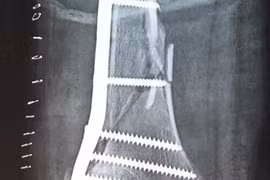

(Kiến Thức) - Gãy kín lồi cầu xương đùi là tổn thương nội khớp thuộc khớp gối, nguyên nhân do chấn thương, hậu quả để lại là hạn chế vận động khớp, cứng khớp, thậm chí có thể mất chức năng gấp duỗi khớp.